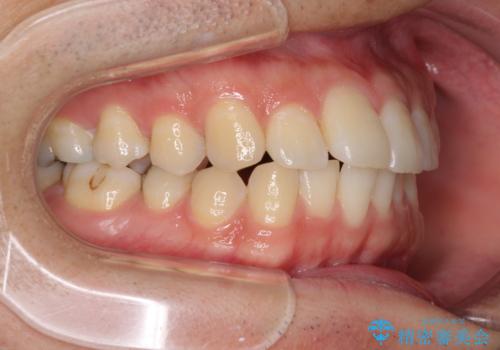

インビザライン・ライトによる矯正治療の後戻り改善

- 矯正治療の後戻りを気にして来院された患者様です。

後戻りは軽微でしたので、インビザライン・ライトにより矯正治療を行うこととしました。

再矯正後の後戻りを防ぐため、歯列排列後に、下顎前歯はワイヤーによる固定を行いました。

下顎前歯の歯列を動かないようにしておくことで、上顎前歯の後戻り防止にも効果を発揮します。